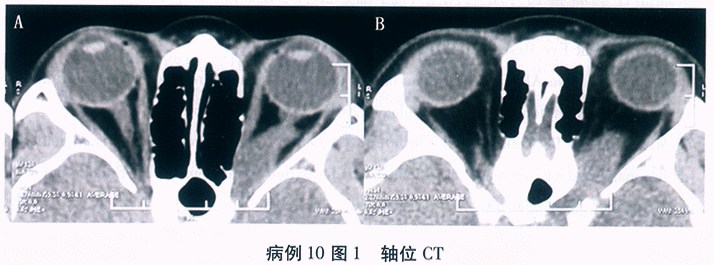

共聚焦显微镜观察睑板腺腺泡的改变, 如图10-3、图10-4所示。

(4)辅助检查共聚焦显微镜观察睑板腺腺泡发现左眼睑板腺泡密度下降和萎缩,右眼睑板腺泡密度下降及阻塞性腺泡增大

基于以上几点分析:双眼睑板腺功能障碍,双眼睑缘炎相关角结膜病变。